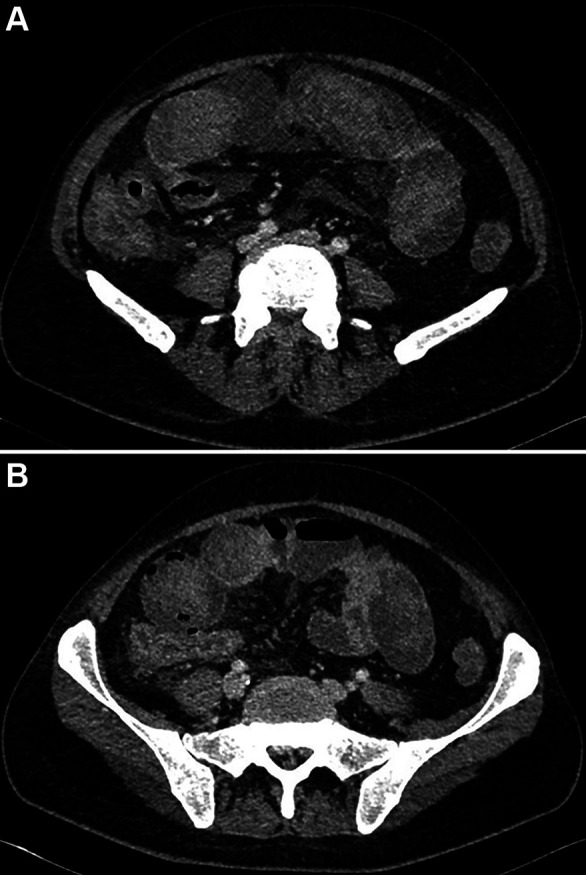

Case report: We report the case of a 44-year-old male with acute myeloid leukemia (AML) and intestinal Behçet's disease who developed severe NE during induction chemotherapy. Initial conservative management was guided by serial cross-sectional imaging, which revealed progressive bowel wall thickening, pneumatosis intestinalis, and signs of ileus. The clinical course was complicated by septic shock, multiorgan dysfunction, and later, acute gastrointestinal hemorrhage. Active arterial bleeding was identified via computed tomography angiography and successfully treated with interventional radiological coil embolization. Surgical intervention was avoided. Multidisciplinary collaboration, including hematology, radiology, rheumatology, intensive care, and pain management, was essential in navigating this complex clinical scenario.